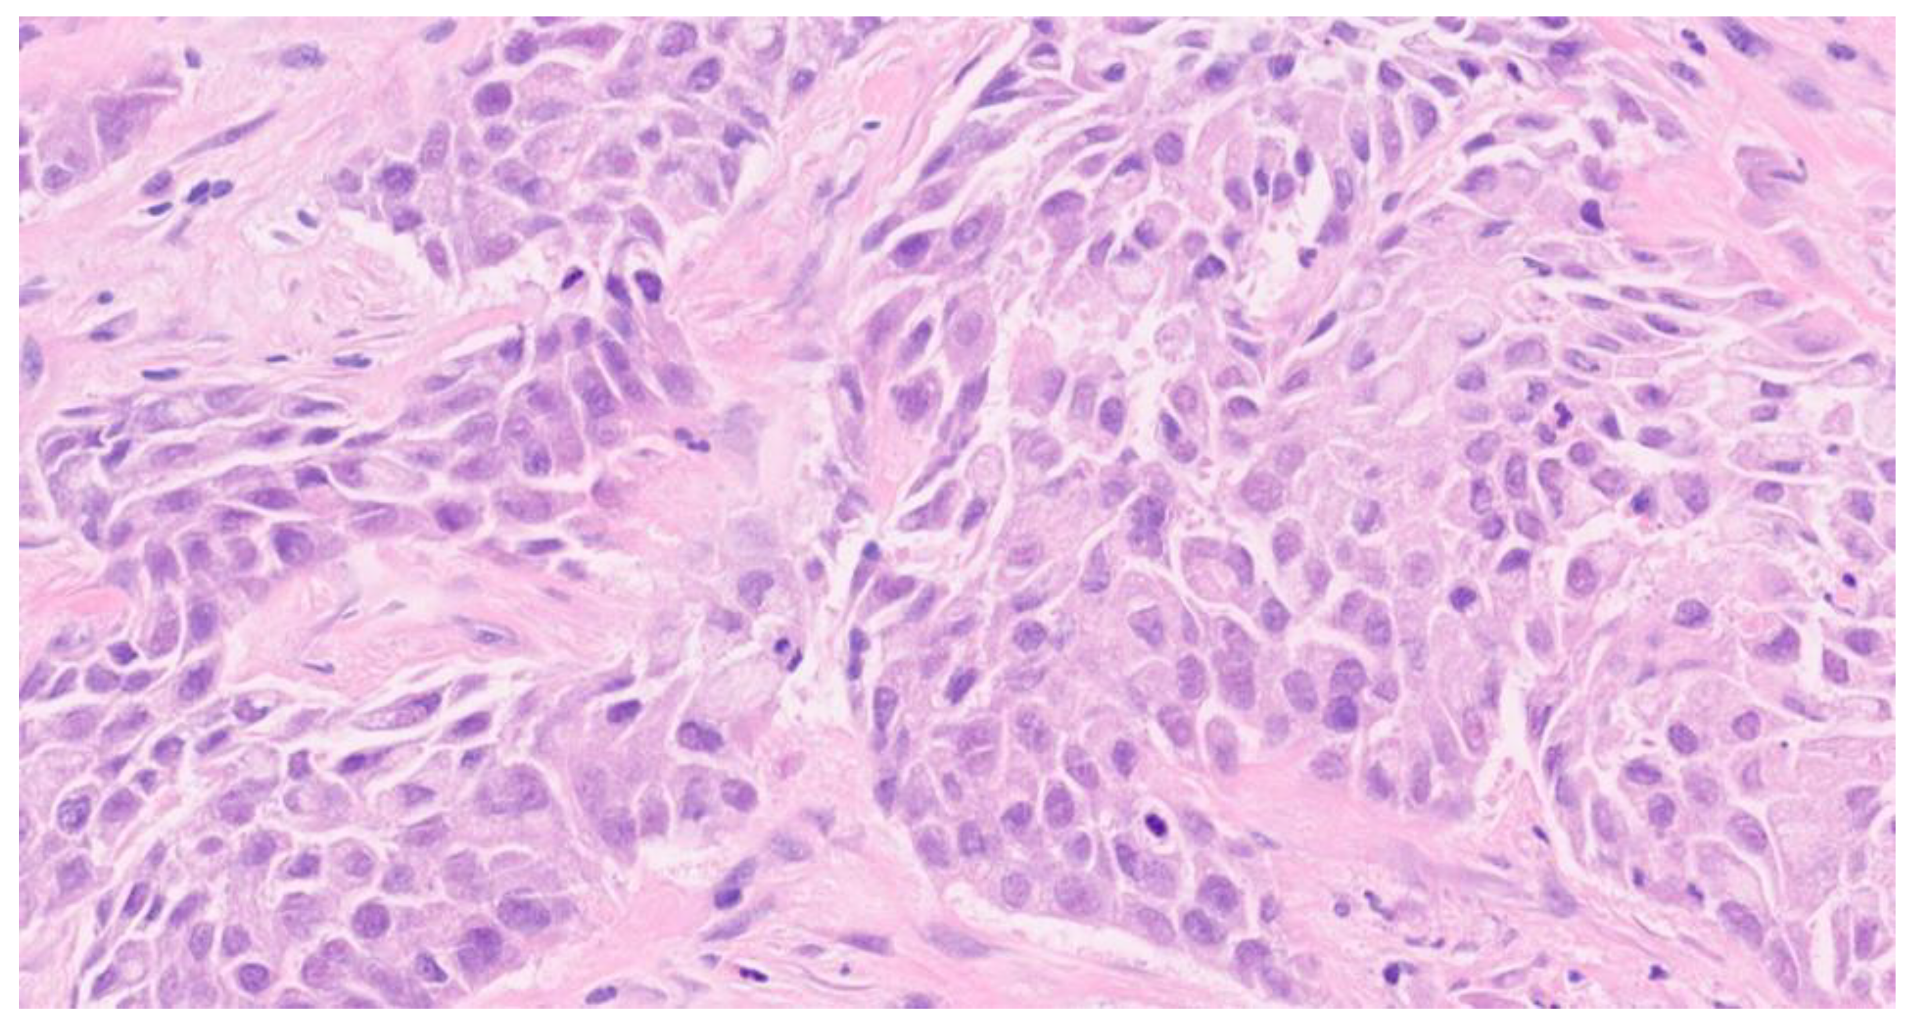

On May 2024, the histological examination revealed the presence of carcinoma, specifically involving the bronchial mucosa, which showed infiltration near the cartilaginous tissue by a neoplasm with solid and glandular growth and widespread expression of cytokeratin 7 (Figure. 3) Overall, the histopathological findings were substantially similar to those of the previous histological examination that involved the breast (Figure 4, Figure 5 and Figure 6). The pathologists performed further examinations on the breast and lung biopsies, testing for TTF1 (Thyroid Transcription Factor-1) commonly tested for in various types of neoplasms, primarily to help in the diagnosis and differentiation of lung and thyroid cancers (specifically TTF1 is used to identify lung adenocarcinomas, small cell lung carcinomas and thyroid carcinomas) (Figure 7), GATA3 gene commonly involved in various types of cancers, primarily those arising from epithelial tissues (breast carcinoma, urothelial and in general urological carcinomas, lung carcinomas and thyroid carcinoma and certain hematologic malignancies), napsin A which is an aspartic proteinase enzyme encoded by the NAPSA gene, primarily recognized for its expression in specific cancers, specifically lung adenocarcinoma, and P40, a variant of the p63 protein encoded by the TP63 gene, is identified through its immunohistochemical staining, aiding pathologists in distinguishing squamous cell carcinomas from adenocarcinomas in various tissues, including lung, head, and neck. All these examinations came back negative. PD-L1 (Programmed Death-Ligand 1, important target in anticancer therapy) was absent, and ALK (Anaplastic Lymphoma Kinase, involved in some types of small cell lung cancer), EGFR (Epidermal Growth Factor Receptor, implicated in many cancer types, particularly non-small cell lung cancer), ROS1 gene (primarily involved in non-small cell lung cancer), RET gene (involved in various cancer types, for example medullary thyroid carcinoma), METex14 (specific mutation in the MET (Mesenchymal-Epithelial Transition factor) gene involving exon 14 that can be relevant in non-small cell lung carcinoma) , NTRK1/2/3 (Neurotrophic Tyrosine Receptor Kinase family genes involvede in different types of solid tumors and hematologic malignancies), and BRAF (B-Raf Proto-Oncogene, Serine/Threonine Kinase, involved in different types of cancer especially melanoma and others type of solid tumors) were all wild type (wt).

Figure 5. Hematosylin eosin 20x.

Preprints 112940 g005

Figure 6. Hematosylin eosin 40x.

The definitive diagnosis came from the endoscopic lung biopsy, which identified a carcinoma involving the bronchial mucosa with infiltration near cartilaginous tissue, displaying both solid and glandular growth patterns. The histopathological findings, which were similar to those seen in the breast tissue, suggested a primary pulmonary origin.